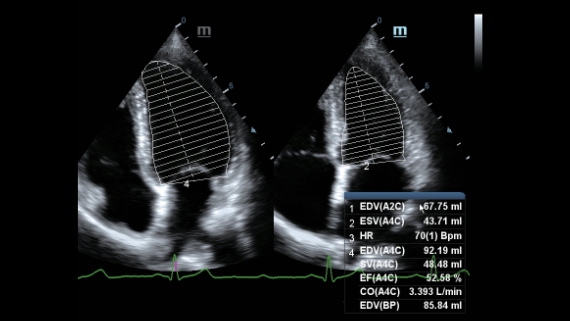

Klinische Bilder